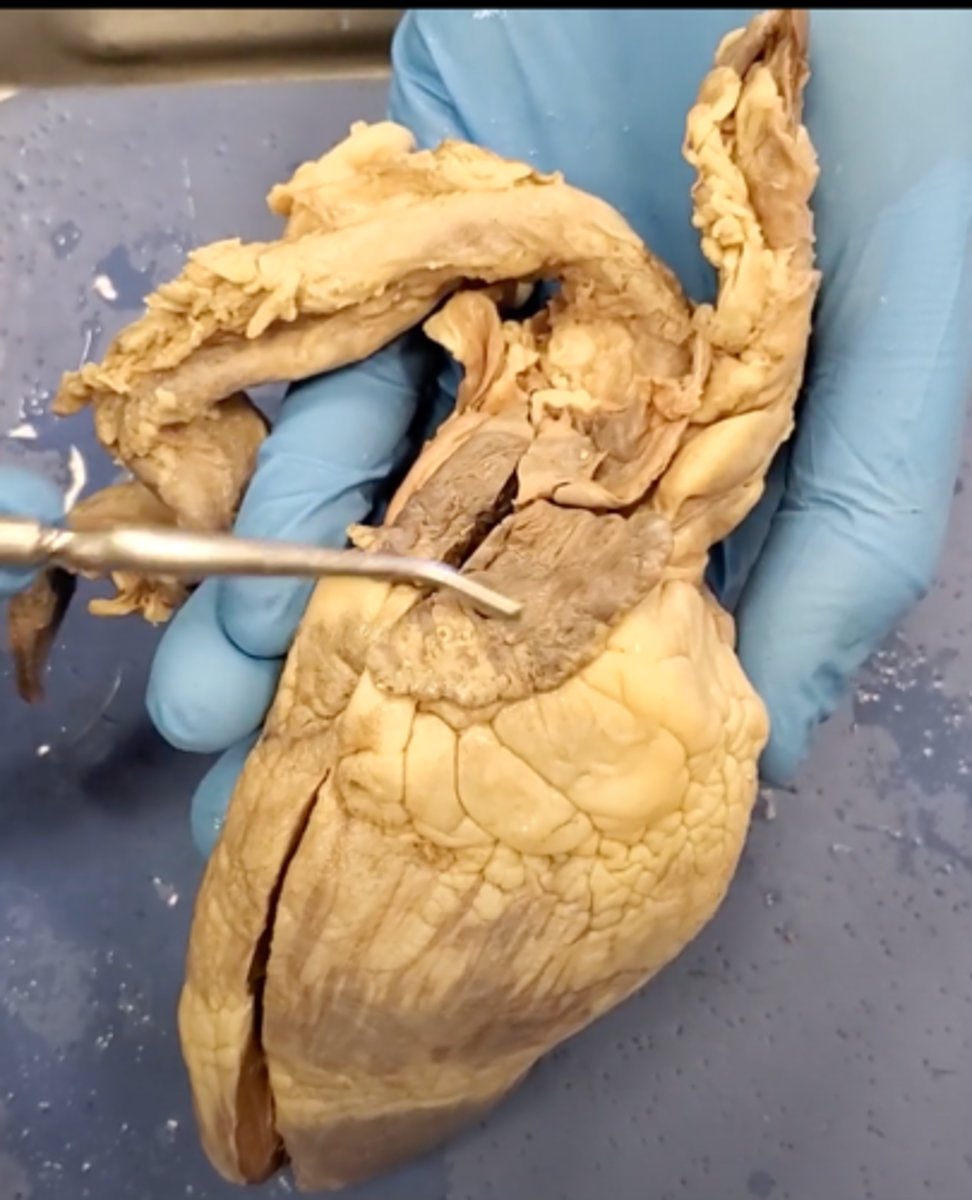

Tricuspid Valve (Right Atrioventricular Valve)

1-valve

Bicuspid valve (Left Atrioventricular Valve)

2-valve

Pulmonary Semilunar Valve

3-valve

Aortic Semilunar Valve

4-valve

Right Atrium

1-chamber

Left Atrium

2-chamber

Right Ventricle

3-chamber

Left Ventricle

4-chamber

bicuspid valve (dissection)

tricuspid valve (dissection)

aortic semilunar valve (dissection)

located between the left ventricle and the aorta

chordae tendineae (dissection)

thin bands of fibrous tissue that attach to the valves in the heart and prevent them from inverting